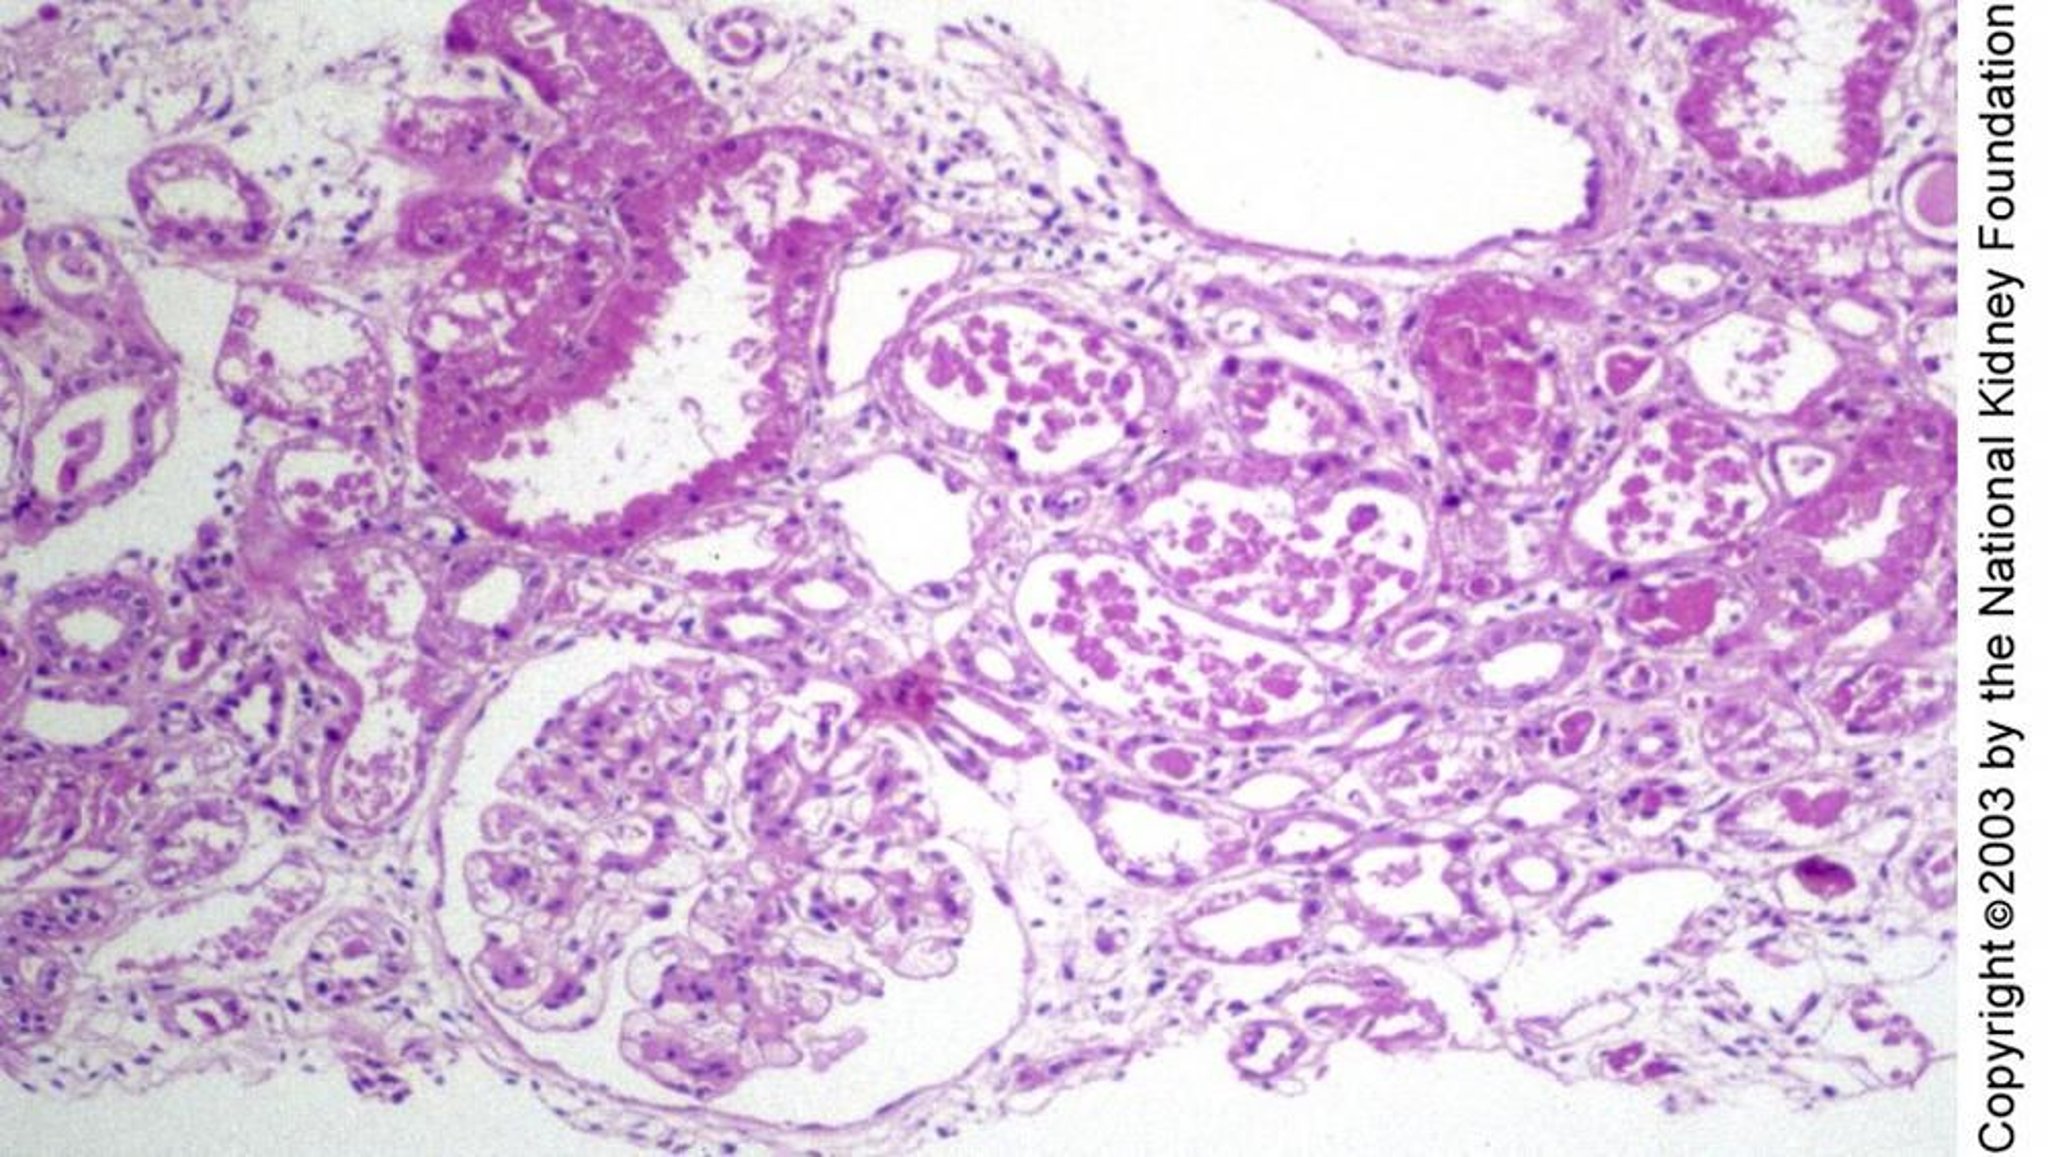

Akute Tubulusnekrose

Die tubuläre Schädigung bei akuter tubulärer Nekrose kann sich histologisch als regenerierendes, abgeflachtes Tubulusepithel ohne Nekrose, wie rechts vom Glomerulus zu sehen, als Blasenbildung und Degeneration einzelner Zellen, wie oben links, oder als offene Nekrose, wie in der Mitte des Bildes, zeigen (periodische Säure-Schiff-Färbung, ×100).

Image provided by Agnes Fogo, MD, and the American Journal of Kidney Diseases' Atlas of Renal Pathology (see www.ajkd.org).